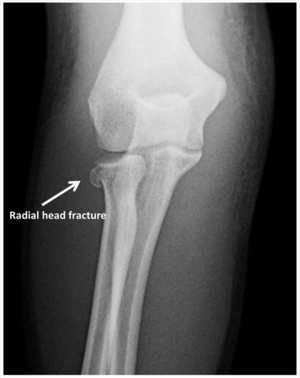

- Radial head fracture

- AP and lateral elbow xray